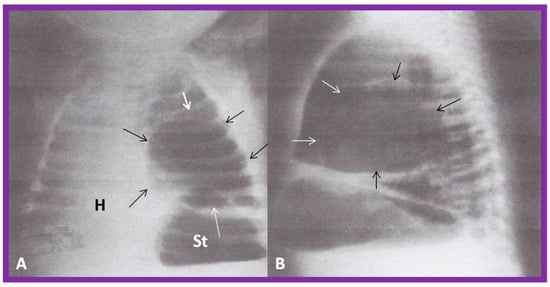

5.2.3. Tracheobronchial Tree Pattern

In typical patients with situs solitus, the bronchus on the right side is short and wide and descends somewhat steeply, whereas the bronchus on the left side is longer and narrower than the right bronchus and descends rather horizontally (Figure 22A and Figure 23). On the contrary, in patients with situs inversus, the tracheobronchial tree configuration is inverted (Figure 22B and Figure 24) [2,3,4,5]. The tracheobronchial tree pattern seems more correct than the above two approaches to identifying the atrial situs [2,26,27]. Tomography has been used in the past [27] to more accurately determine bronchial morphology and measure the bronchial lengths but is not routinely used at the present time because of increased radiation exposure associated with tomography and the availability of other imaging studies.

Figure 22. Diagrammatic depiction of the anatomy of the tracheobronchial tree. (A) In patients with situs solitus, the right bronchus is short and wide and inclines somewhat steeply, whereas the left bronchus is long and narrow and traverses in a horizontal pattern. (B) In patients with situs inversus, the configuration of the bronchial pattern is inverted; the morphologic right bronchus is on the left side, while the morphologic left bronchus is on the right side. (C) In patients with heterotaxy (asplenia syndrome), both right and left bronchi have the morphology of the right bronchus. (D) In subjects with heterotaxy (polysplenia syndrome), both the right and left bronchi have the appearance of morphologic left bronchi. Concept is derived from Reference [2], and the Figure is modified from Reference [5].